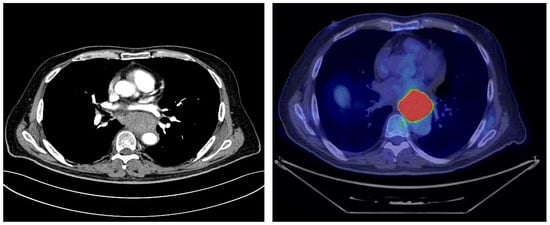

3. Clinical Case